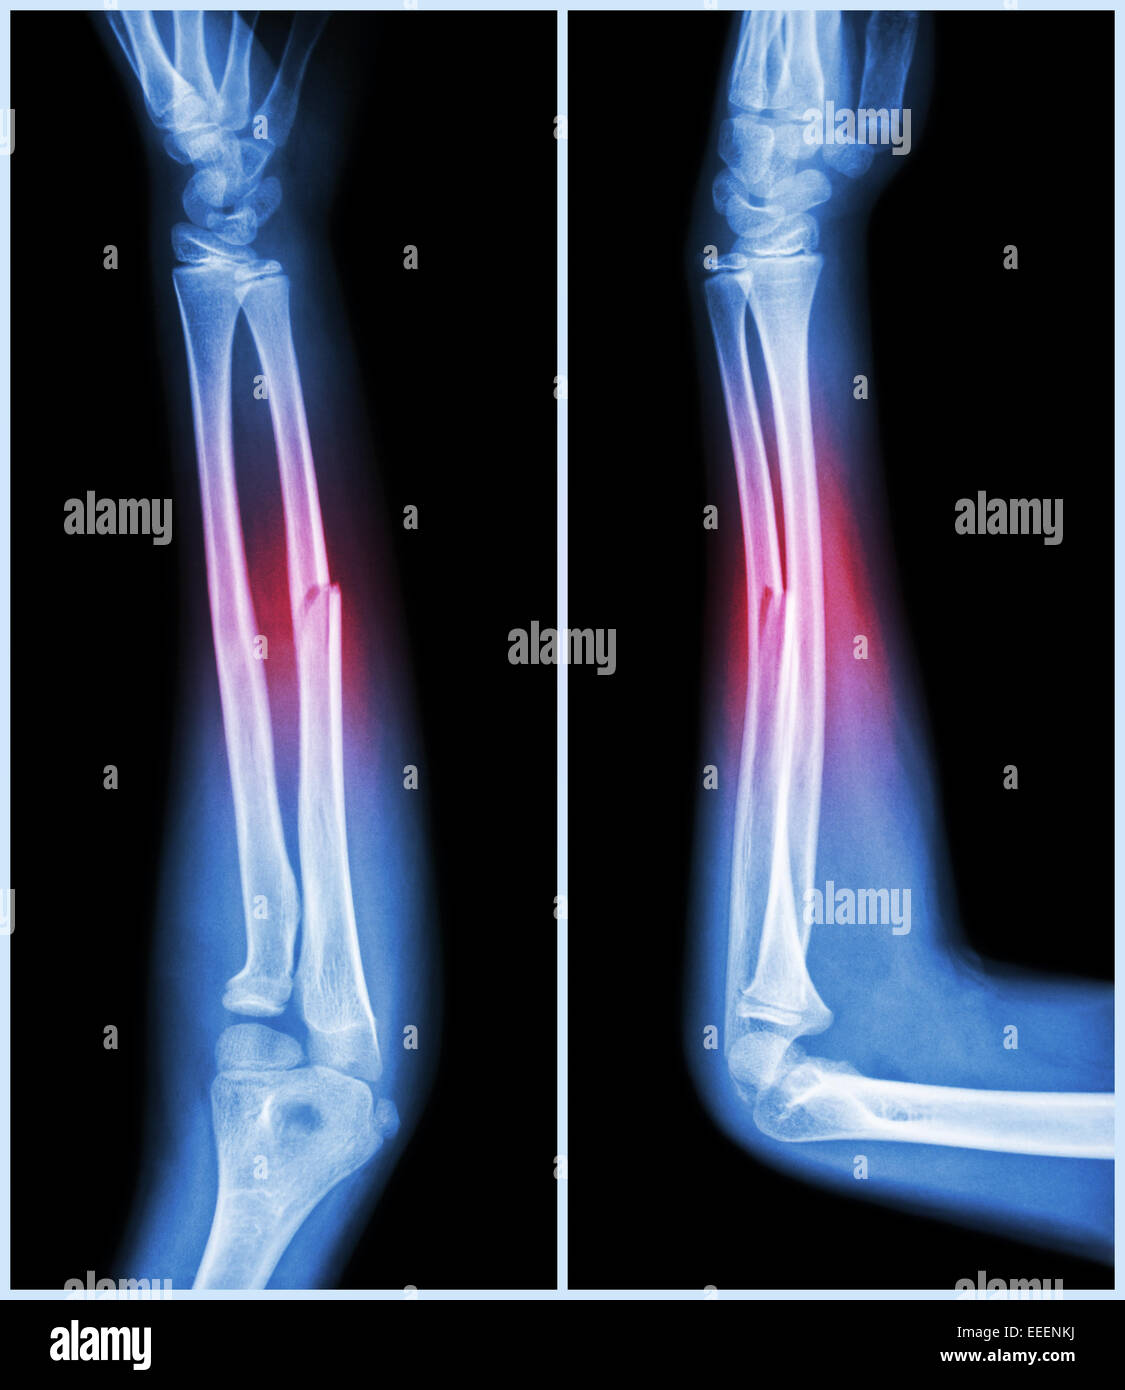

From www.alamy.com

Fracture shaft of ulnar bone ( forearm bone ) ( front and side view Light Bone Fracture The hematoma serves as a scaffold for. Bone fractures usually result from a high force impact or stress. A bone fracture is a crack or break in a bone. Red light therapy stimulates osteoblast activity and mineralization, accelerating bone deposition and remodeling. People with osteoporosis or bone cancer may experience. The case hospitalized for conventional surgery and followed by applying. Light Bone Fracture.